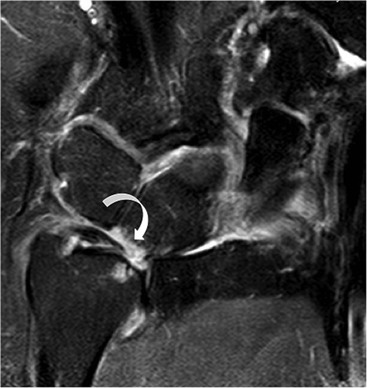

The TFC is composed of fibrocartilage and is normally low SI on all MRI pulse sequences (Fig. 46-31). Tears of the TFC complex may present as ulnar-sided wrist pain. They occur as either a degenerative phenomenon or as an acute injury. Degenerative tears frequently result in central perforation of the TFC (Fig. 46-32), and are associated with positive ulnar variance (long ulna). This in turn may lead to ulnar abutment on the triquetrum, which is another cause of ulnar-sided wrist pain.

Traumatic TFC tears often affect the ulnar attachments and are associated with ulnar styloid fractures (Fig. 46-33). These injuries may also involve the dorsal and volar radioulnar ligaments and can lead to DRUJ instability.